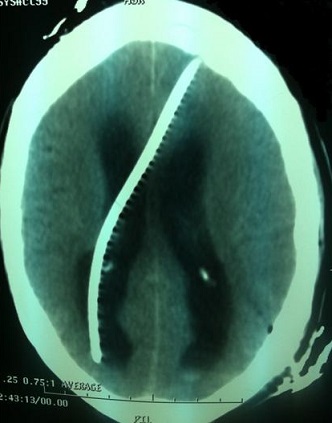

La maîtrise des techniques chirurgicales de dérivations liquidiennes a totalement modifié leur pronostic. Cependant, qu’elle soit péritonéale ou atriale la dérivation du liquide cérébrospinal (LCS) n’est pas un geste anodin puisque plusieurs types de complication ont été décrits. Nous rapportons une migration de l’extrémité proximale du cathéter de dérivation ventriculopéritonéale dans la cavité ventriculaire